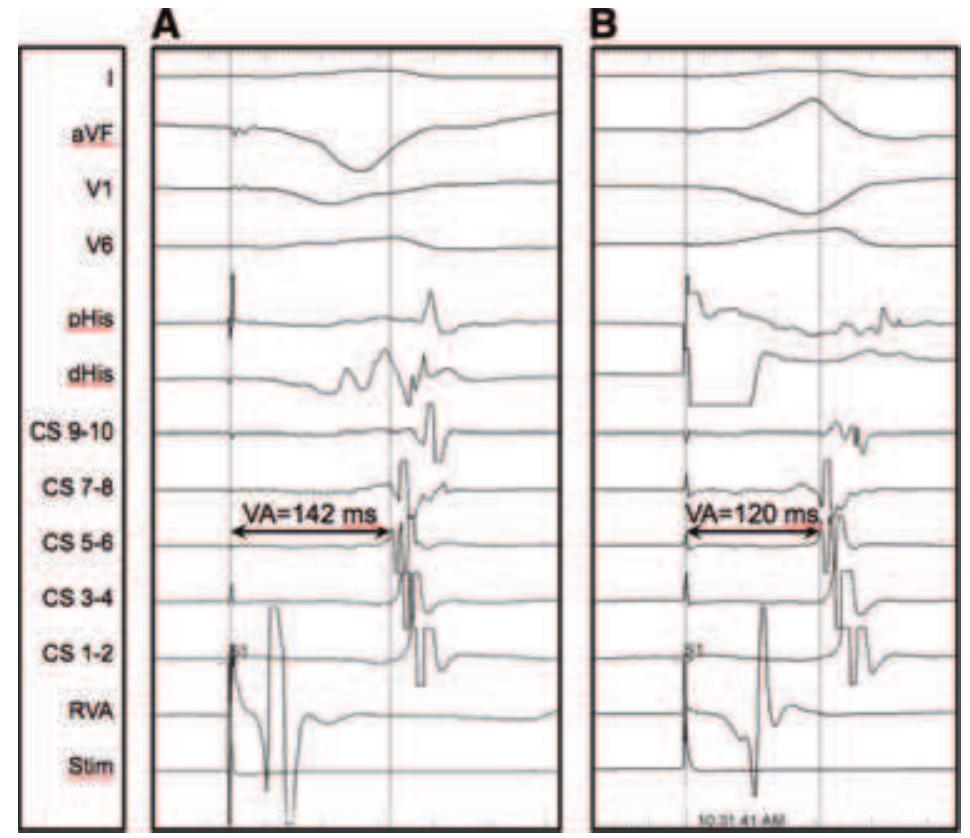

The approach to supraventricular tachycardia (SVT) diagnosis can be complex because it involves synthesizing baseline electrophysiologic features, features of the SVT, and the response(s) to pacing maneuvers. In this two-part review, we... more

![Figure 3. Responses to para-Hisian pacing. In both panels, pacing is being performed from the distal poles of the His catheter (dHis). The first beat in each panel captures the His bundle and local ventricular myocardium (narrow QRS complex), whereas the second beat loses His capture and only stimulates ven- tricular myocardium. Panel A shows the response when retrograde conduction is occurring over a concealed accessory pathway; with loss of His capture there is no change in the SA interval (the time from stimulus [dotted line] to earliest atrial activation [dashed line]), nor is there a change in the atrial activation sequence. In this case, a right para-Hisian pathway was present, with earliest atrial activation on the HRA catheter. Panel B shows the response after successful ablation of the accessory pathway, demonstrating the response when purely AV nodal retrograde conduction is present. With loss of His capture the SA interval extends by 61 ms since the stimulated wavefront must now travel through ventricular myocardium, penetrate the distal branches of the His-Purkinje system, then travel retrogradely through the AV node. Earliest atrial activation is tied between the proximal bipole of the His catheter (pHis) and the CS os (CS 9-10). HRA = high right atrium; CS = coronary sinus; RVA = right ventricular apex; QRSd = QRS complex duration (ms); SA = time from stimulus to atrial electrogram (ms).](https://figures.academia-assets.com/36312953/figure_003.jpg)